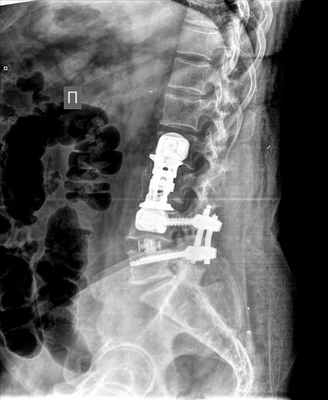

Рис 7. Рентгенография позвоночника в боковой проекции. Улучшение параметров сагиттального баланса. Восстановлен поясничный лордоз. Улучшились параметры позвоночно-тазовых взаимоотношений.

Рис 8: Улучшение показателей сагиттального баланса после операции

В результате проведенного оперативного лечения на устранен фораминальный стеноз на уровне L 4-5, выполнена декомпрессия корешков L 4, L 5, устранена посттравматическая кифотическая деформация позвоночника на уровне L 3, восстановлен сагиттальный баланс, стабилизированы позвоночно-двигательные сегменты L 2-3, L 3-4, L 4-5; прошла корешковая боль и симптомы нейрогенной перемежающейся хромоты, уменьшилась боль в поясничном отделе позвоночника. После операции нарастания неврологического дефицита нет. Послеоперационные раны заживают первичным натяжением. Пациентка выписана с рекомендациями на амбулаторное лечение на 11 сутки после второго этапа оперативного вмешательства без осложнений.